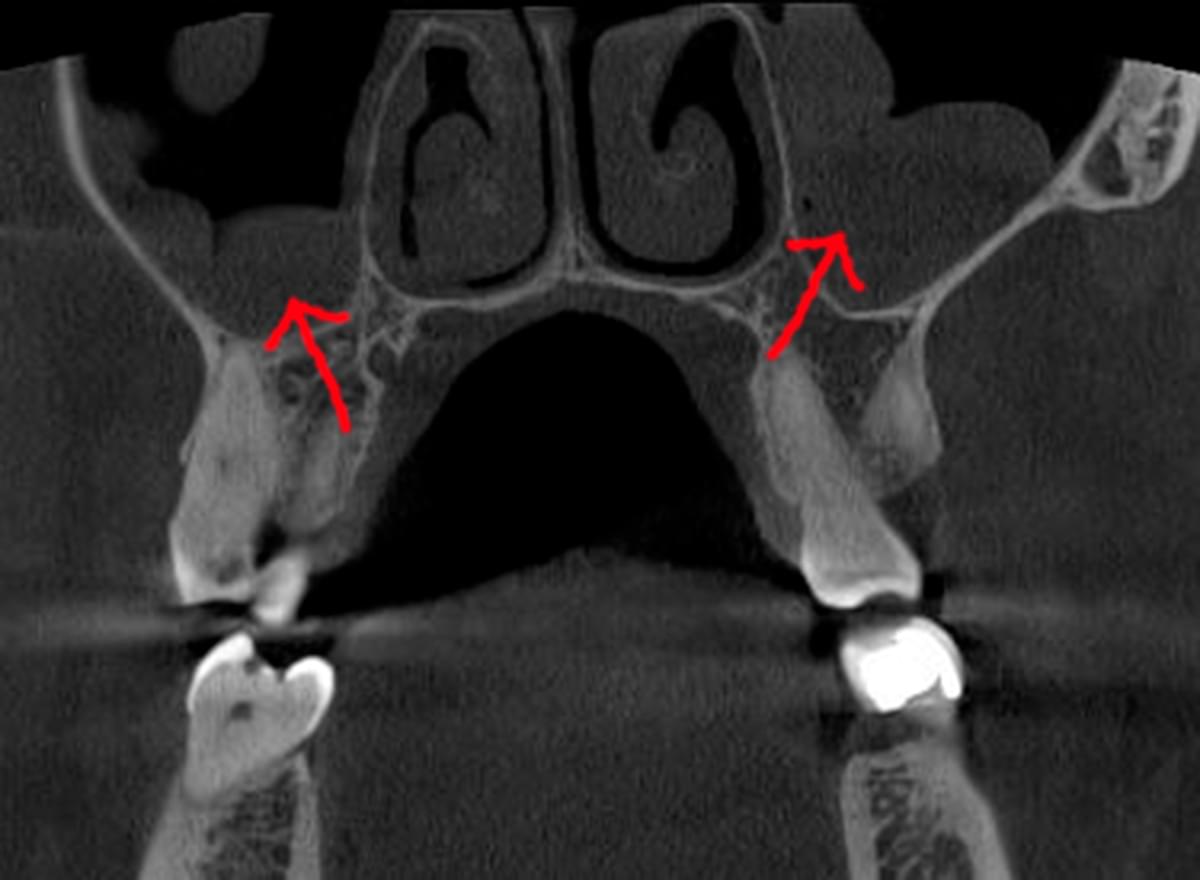

Головний недолік 2D-рентгену — це площинне зображення. Зуби, корені, щільна кістка та гайморові пазухи накладаються один на одного, створюючи «візуальний шум».

Часто причиною зубного болю є гайморит, і навпаки — причиною запалення пазух є хворий зуб. На звичайному знімку пазуха виглядає як темна пляма. На КТ ми бачимо стан слизової, наявність кіст або сторонніх тіл (наприклад, залишків пломбувального матеріалу), що критично важливо для правильного діагнозу.